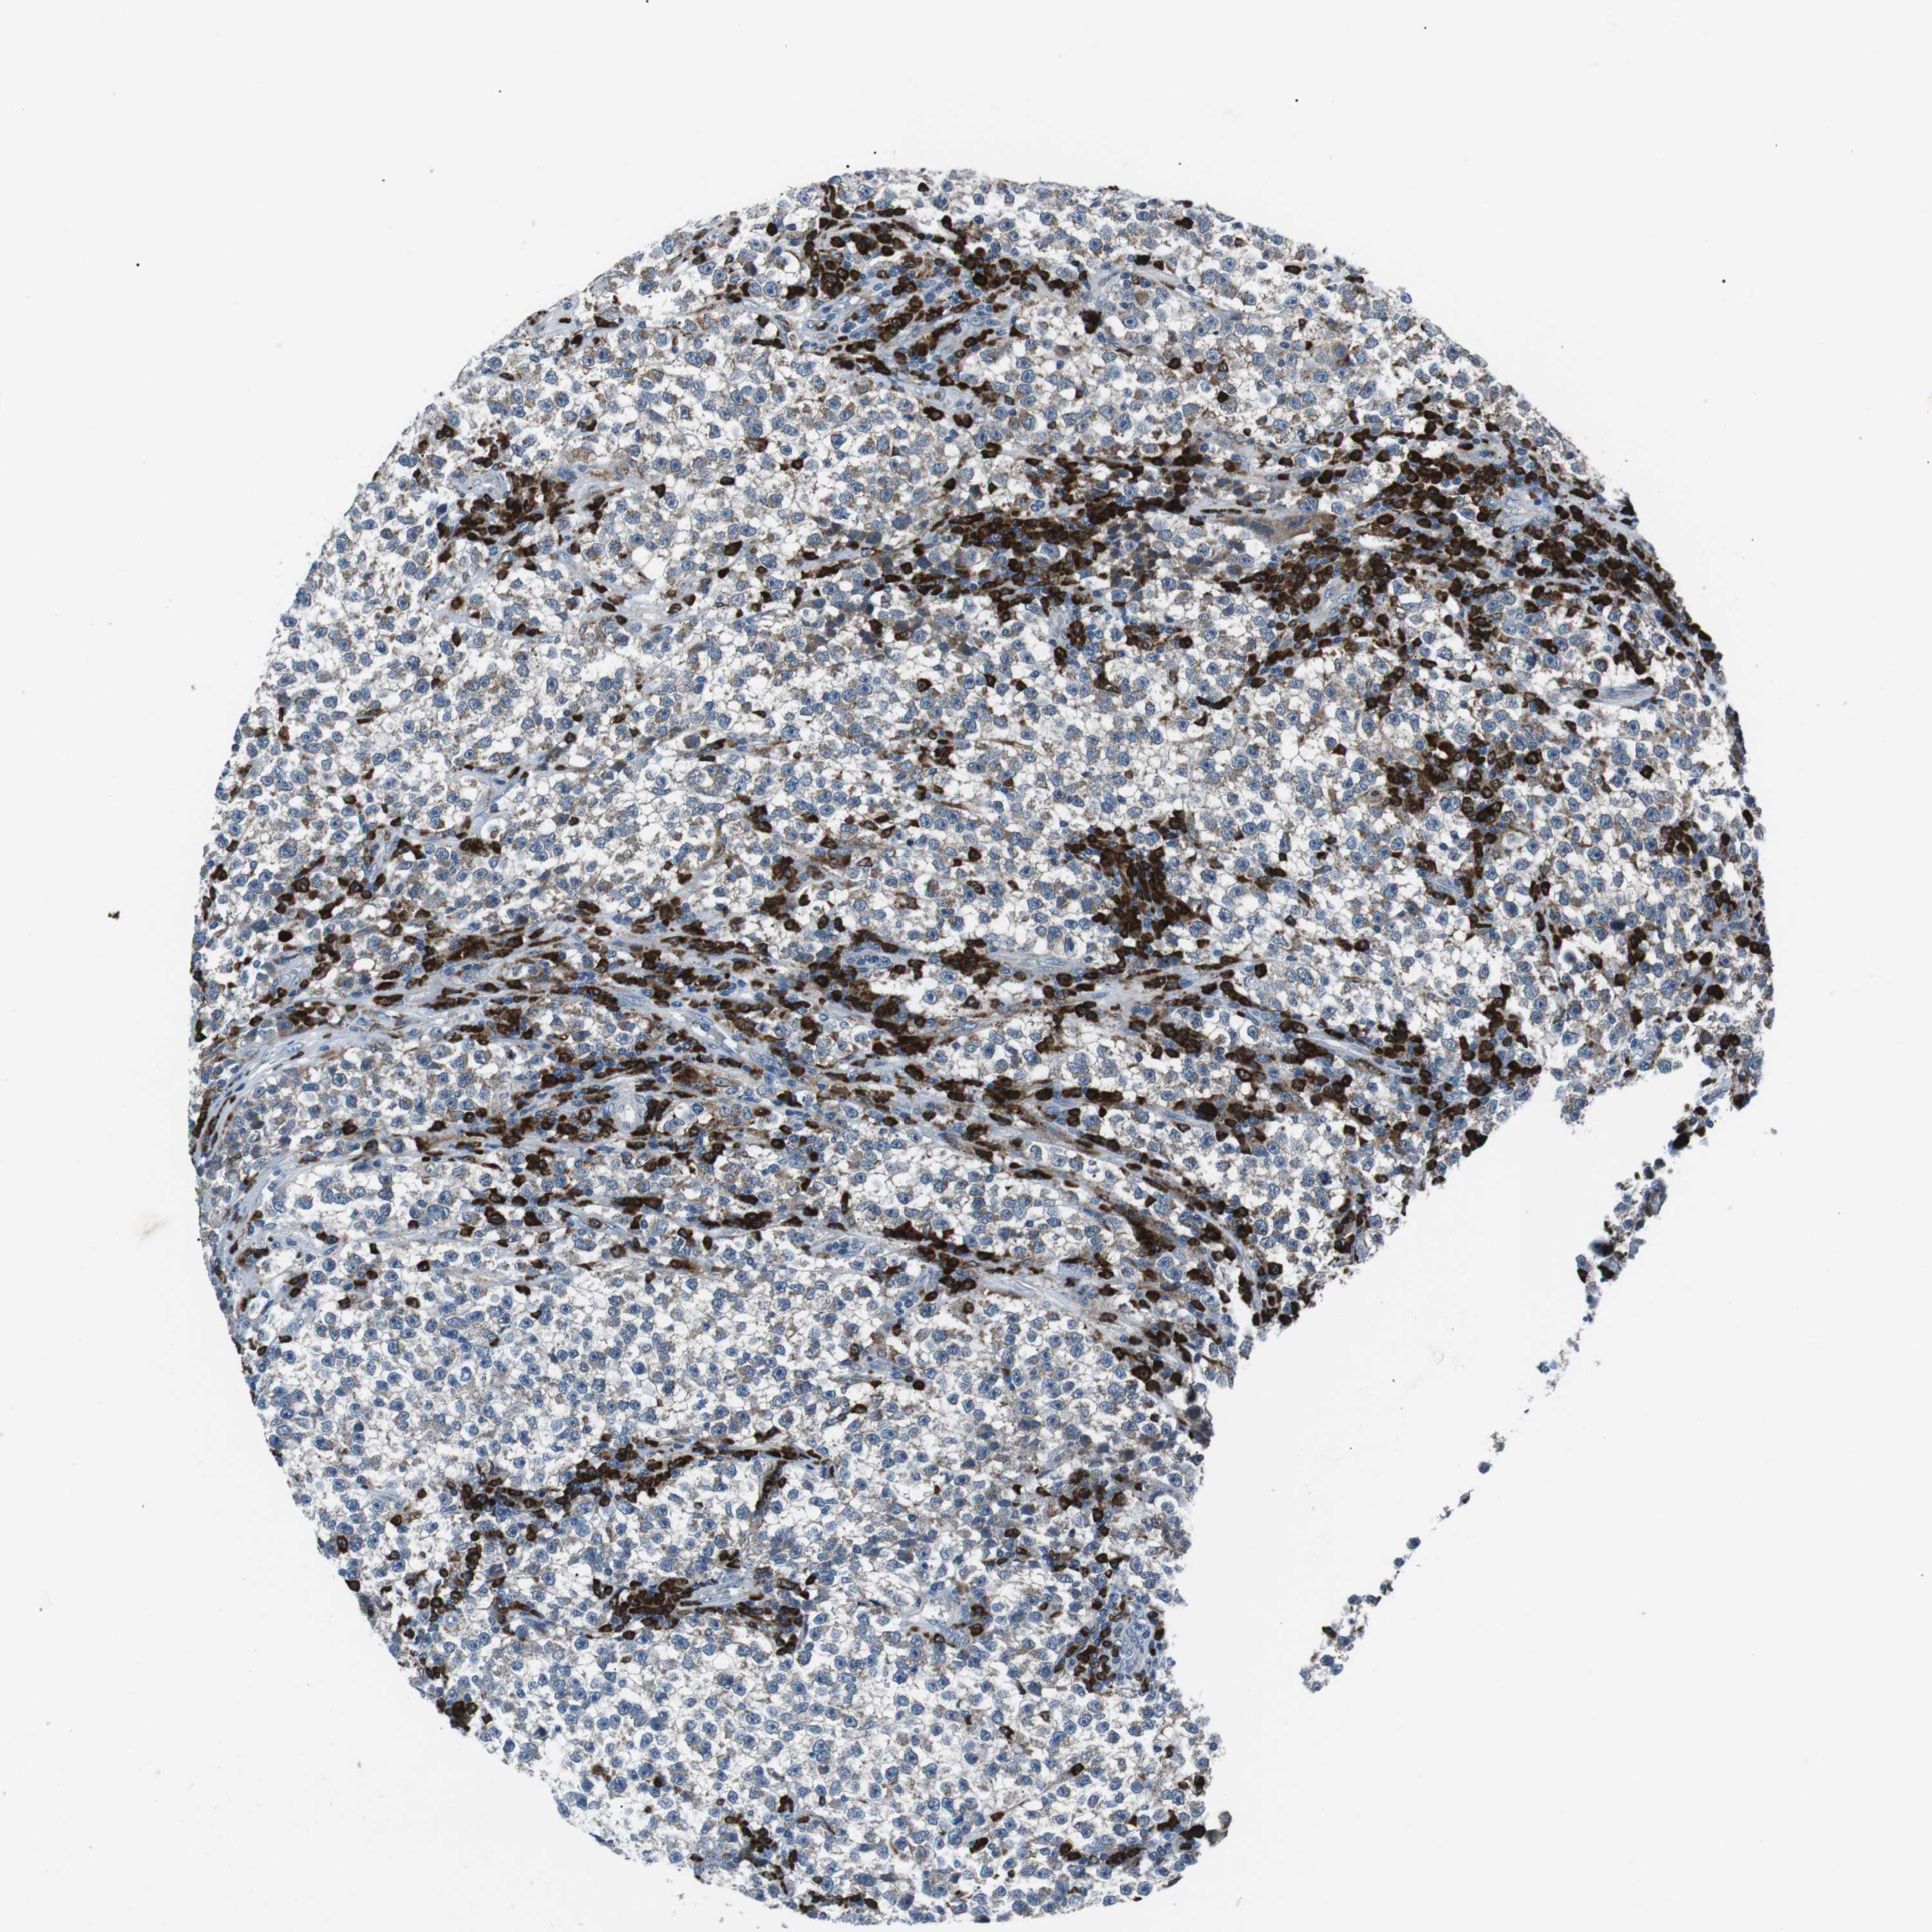

TESTIS CANCER - Protein expressioni

A mouse-over function shows sample information and annotation data. Click on an image to view it in a full screen mode. Samples can be filtered based on level of antibody staining by selecting one or several of the following categories: high, medium, low and not detected. The assay and annotation is described here.

Note that samples used for immunohistochemistry by the Human Protein Atlas do not correspond to samples in the TCGA dataset.

Antibody stainingi

Antibody staining in the annotated cell types in the current human tissue is reported as not detected, low, medium, or high, based on conventional immunohistochemistry profiling in selected tissues. This score is based on the combination of the staining intensity and fraction of stained cells.

Each image is clickable and will lead to virtual microscopy that enables deeper exploration of all samples and also displays staining intensity scores, fraction scores and subcellular localization as well as patient and tissue information for each sample.

Antibody HPA038309

Antibody HPA038310

Antibody CAB009333

Antibody CAB016291

Carcinoma, Embryonal, NOS

Seminoma, NOS

Urothelial carcinoma, High grade